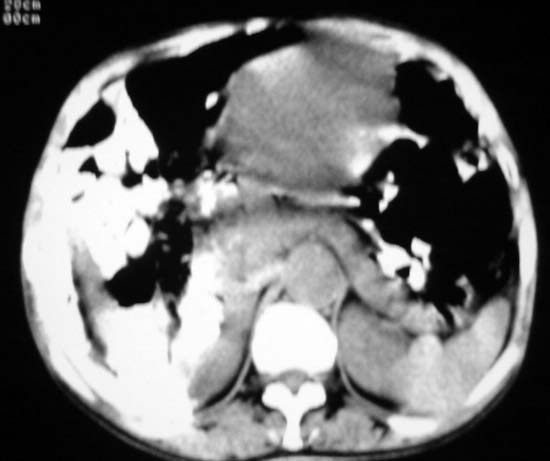

女,75岁,腹部胀大半年余,无其他症状。

考虑来源与卵巢的巨大囊腺瘤或囊肿。

ct值各是多少?考虑卵巢囊肿或囊腺瘤。

考虑来源于卵巢的巨大囊腺瘤;如果是单纯囊肿不知其前部的更低密度区怎么解释?

考虑来源卵巢巨大黏液性囊腺瘤。